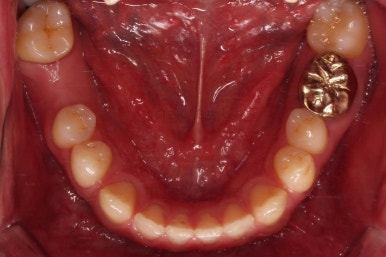

거의 모습이 완성되었습니다.

교정치료도 종료 되었고 연산동임플란트 잘 완성이 되었어요.

총 14개월이 걸린 치료였는데 비교적 짧은 기간 내에 틈새도 모으고, 임플란트 및 충치치료도 다 완료를 할 수 있었습니다.